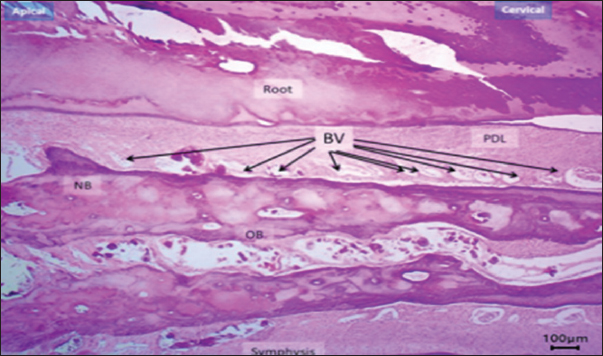

Based on the histomorphometric findings, exogen treatment markedly enhanced bone-forming activity, as evidenced by a statistically significant increase in osteoblast count at both day 10 and 20 compared with the control group (p < 0.01), indicating accelerated bone formation. In contrast, osteoclast count was significantly reduced at day 20 (p < 0.05), reflecting suppression of bone resorption. Vascular density showed a consistent and significant increase across all post-removal time points (p < 0.01), providing a more favorable blood supply for bone and periodontal tissue healing. Additionally, PDL width was narrower in the Exogen group by day 20, suggesting enhanced tooth stability after orthodontic appliance removal. Representative histological sections at day 10 are shown in Figures 7 and 8.

Fig. 7. Histological section of the exogen-treated group at day 10 showing a broad zone of newly formed bone (NB) with aligned osteoblasts (arrows). H&E stain, 40×, scale bar=100 μm.

Fig. 8. Histological section at day 10 (non-Exogen group) showing multiple blood vessels (BV) within newly formed bone (NB). H&E stain, 40×, scale bar=100 μm.

This pattern of results translates into accelerated healing of bone and periodontal tissues with an improved vascular environment, supporting the hypothesis that LIPUS can reduce post-treatment tooth relapse and promote long-term stability (Fig. 9a and b). New bone surface distribution is demonstrated in Figure 10.